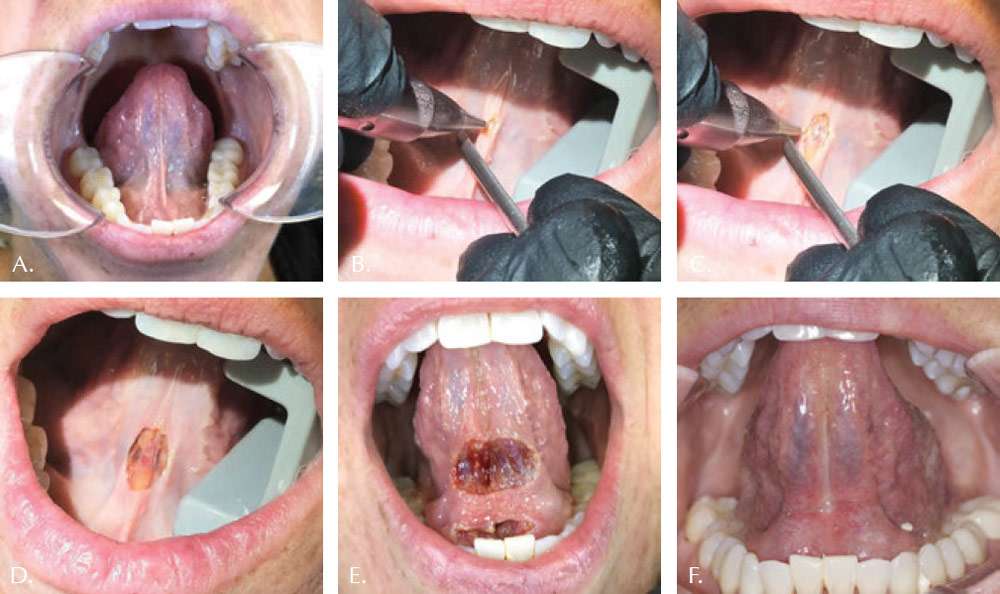

The osteopathically guided Functional Frenectomy (for both labial and lingual restrictions) is illustrated by the clinical case shown in Figures 1-3. Note both the immediately improved mobility and lift of the tongue. The well controlled hemorrhage, sealed lymphatics and reduced zone of thermal impact result in less edema and discomfort to the patient. Magnification during the frenectomy is strongly encouraged due to the close proximity of large blood vessels to the surgical site. The authors prefer using topical anesthesia to increase the reliability of the functional assessment during the release. However, the patient in this case felt the laser at times and small amounts of local anesthetic were administered to the upper and lower frenectomy sites.

In order to achieve the proper myofascial release in adult patients, it is not sufficient to just remove the aberrant frena. Under the osteopathic guidance, the clinician should often re-access the effect of the restriction release on other myofascial structures. The clinician must take into account the jaw range of motion, the floor of the mouth flexibility, along with the tongue’s ability to elevate, protrude, and achieve lateral functions. The clinician should proceed slowly and cautiously. It is important to remember that full range of motion is not always possible due to other limitations, i.e., clinician needs to know when to stop to achieve the maximum benefit. Frenum that restricts proper lingual or labial motion feels tight to finger pressing in. Unrestricted tongue and lips feel soft. To feel for restrictions, one can grasp the tip of tongue or lip with gauze and gently pull the tongue upwards and the lip outwards. Finger pressure of the other hand could help reveal accessory restrictions as push back would be felt. In this case study, the clinician used the tongue director as a probe to apply pressure to the points that appeared restrictive, and removed those fibers, or not, depending on the real-time osteopathic feedback from Dr. Geis.